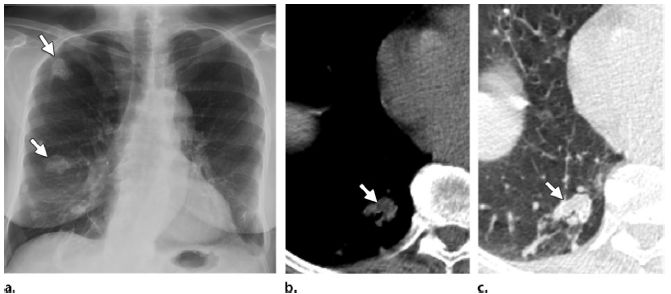

图2 女,67岁,结节型实质淀粉样变性(a)胸片显示多发肺结节(箭头),主要位于右肺。(b,c)CT显示一个结节位于右肺基地(箭头在),主要是软组织组织密度衰减,无钙化;患者有明确的淀粉样变性病史。没有钙化时,这种分散的块状淀粉样沉积(淀粉样物)可与原发性肿瘤或转移瘤难以鉴别。